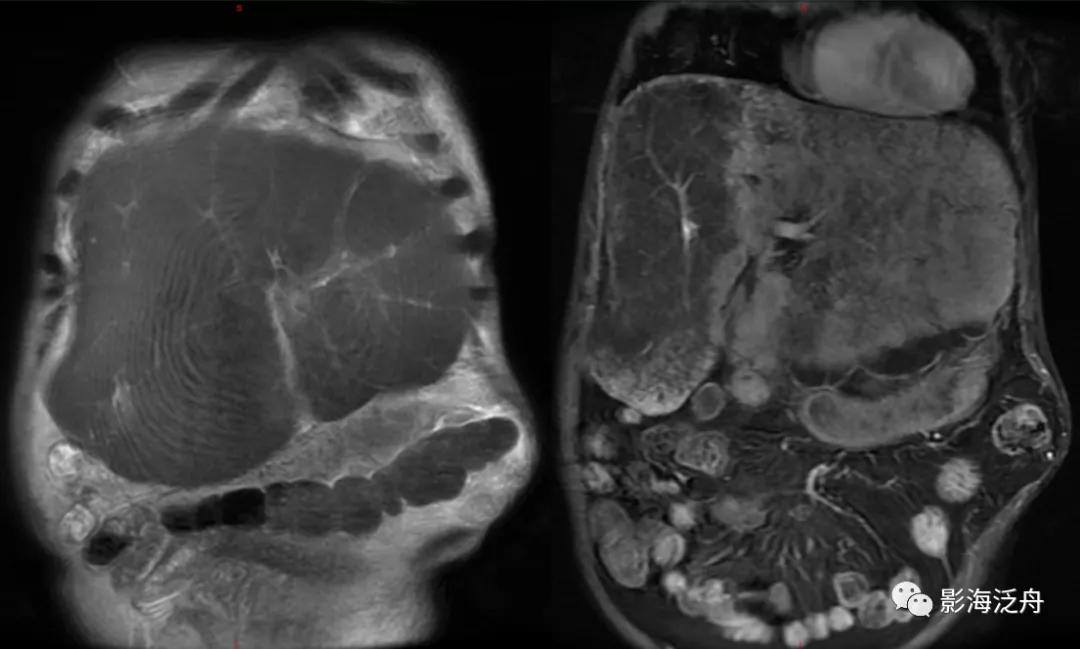

一例比较典型的肝硬化病例:T1WI上呈均匀稍高信号的再生结节(绿箭头)遍布全肝,再生结节在T2WI上呈明显低信号,这种低信号也是由于铁质沉积造成的,再生结节周围的纤维分隔因炎症浸润而呈高信号(红箭头)。

增强延时期,富纤维的肝组织呈较明显强化,而再生结节在纤维化背景肝实质的衬托下呈相对低信号(红箭标注几个较典型的再生结节)。